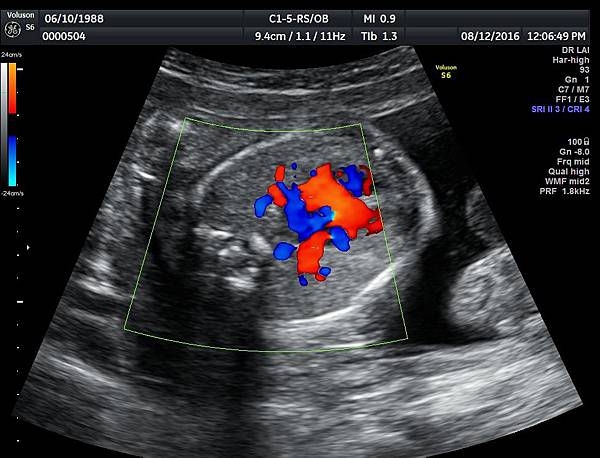

我看肺靜脈的心路歷程可以分成三個階段,第一個階段是用gray scale(黑白)看到左右肺靜脈下行支回到左心房(附圖 1.2.),第二個階段是用flow(彩色)看到左右肺靜脈回到左心房(附圖 3.4.),第三階段是同時要看到黑白和彩色的左右肺靜脈回到左心房,為什麼只有看flow(彩色)不安全呢?因為右肺靜脈的flow有時候是假影,為何會看到假影?因為右心房到左心房的flow overlapping(重疊)造成的(附圖 5.),如何判斷是假影,只要關掉flow看黑白的即可證明右肺靜脈沒有進入左心房(附圖 6.)。

如果同時看到左右肺靜脈進入左心房,這種誤判的機率下降很多,如果只能看到一條肺靜脈的血流,我會選擇左肺靜脈(附圖 7.8.),因為左肺靜脈的血流比較不會被overlapping,最安全的方法是黑白和彩色都看到左右肺靜脈進入左心房,只是需要胎兒姿勢配合,當然孕婦的體重也是需要考量的因素。

2016年10月10日,日本川瀧醫師(Dr Kawataki)在台灣的胎兒心臟超音波 stic seminar(附圖 9.10.)演講時講到一句話,flow and gray scale 同時看肺靜脈進入左心房才不會漏掉肺靜脈回流異常,他一語道破這個眉角,我是花了很多年才得到這個心得,如果川瀧再來台灣,我們要多跟他學習,他是一位有赤子之心的醫師,聽他的演講可以節省很多摸索的時間。